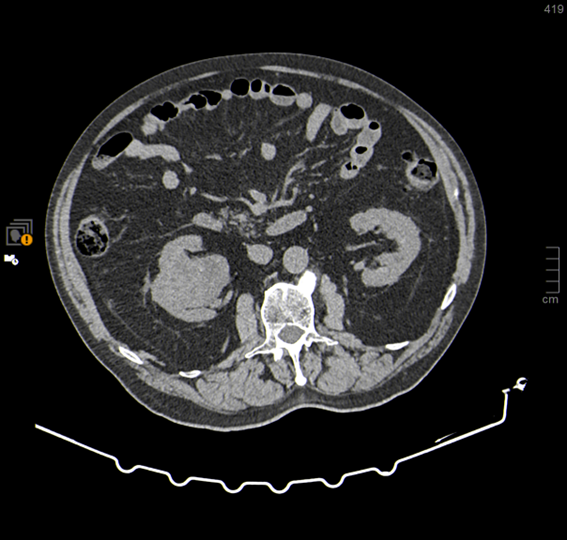

Urotac con contraste IV, fase venosa Urotac con contraste IV, fase excretora

TC simple, con contraste IV y en fase excretora (Uro-TC)